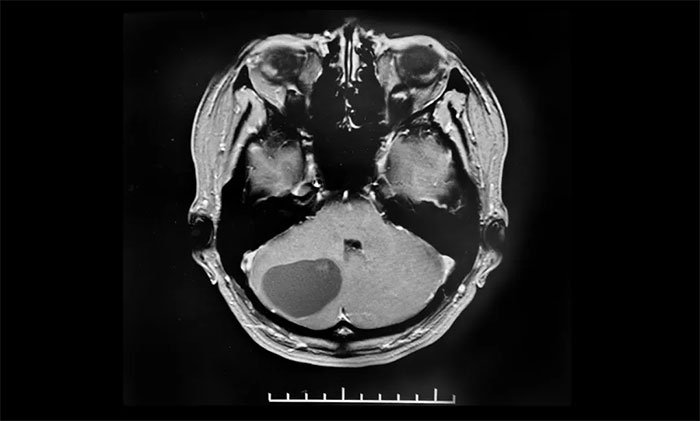

6个月前,小妍在无任何诱因的情况下出现了头晕,一旦发作就觉得天旋地转,2月前在头晕发作时还会出现枕部头疼,10余天前又出现了行走时步态不稳症状。小妍的母亲赶紧将小妍带到了当地医院检查,经行头颅MRI显示,在小妍的左侧小脑半球有一长T1长T2圆形囊实混合占位,大小约4.2*3.2cm,考虑为“脑血管母细胞瘤”,并且合并脑积水,建议其手术治疗。

▲ 右侧小脑血管母细胞瘤,大小约34x34mm